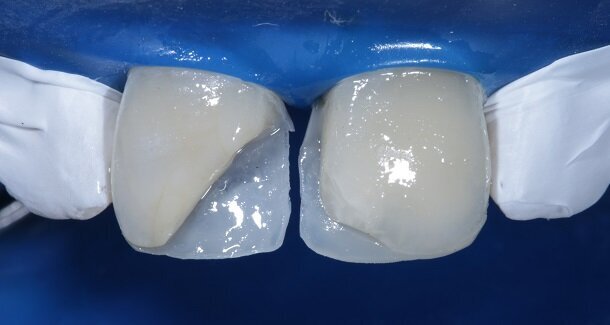

The figures show the clinical work flow involved. In the 1st appointment Oral prophylaxis, oral hygiene instructions were followed by an impression that was sent to the lab for a wax up [Fig 3 and 4]. In the subsequent appointments, Endodontic treatment was followed by Intra and extra coronal office bleaching using the Pola office bleaching kit. After two weeks, the shade stabilised post bleaching. Shade selection, rubber dam isolation and preparation was done on both the teeth to receive Direct composite veneers so as to close the midline diastema as well as correct the fractured teeth and the slight mal-alignment. Controlled Body Thickness (CBT) technique of layering was used with 3M Z350XT shades - Dentin shades A3, A2 and Enamel shades A2, clear translucent [Figures 5 to 11]. This was followed by the Finishing and polishing protocol as described in the figures.

Characterisation begins during Dentin Layering itself. [Fig 9] Shape of the tooth is extremely important. A well-made putty key from a wax-up or a mock-up can help in maintaining shape of the tooth. [Fig 3 and 4]